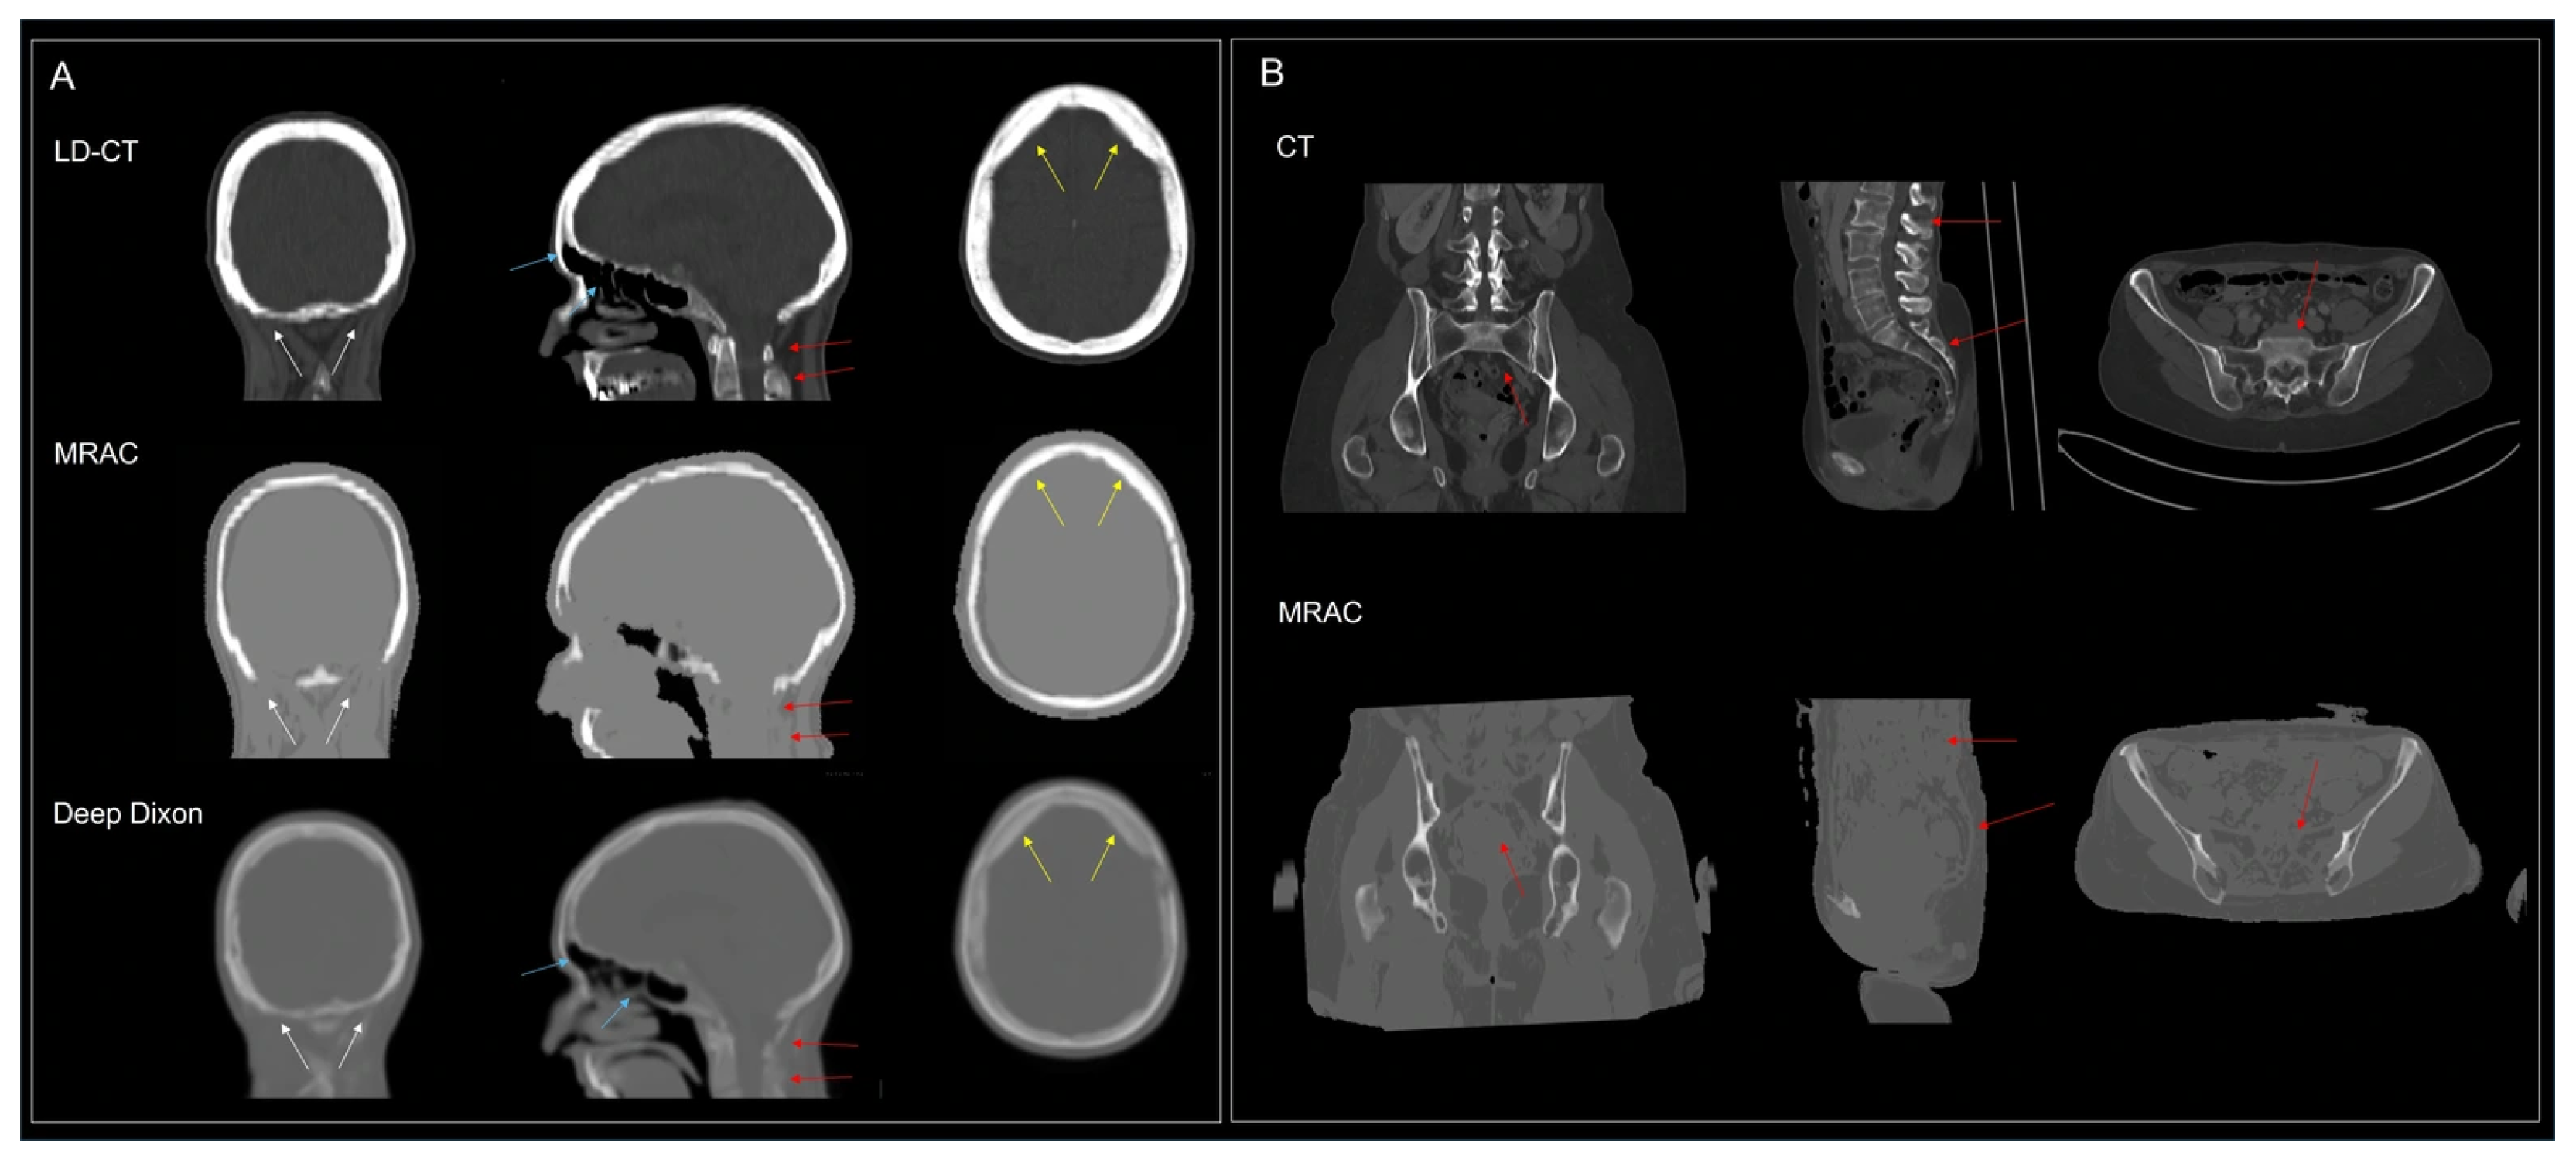

- Ladefoged, C.N.; Hansen, A.E.; Henriksen, O.M.; Bruun, F.J.; Eikenes, L.; Oen, S.K.; Karlberg, A.; Hojgaard, L.; Law, I.; Andersen, F.L. AI-driven attenuation correction for brain PET/MRI: Clinical evaluation of a dementia cohort and importance of the training group size. Neuroimage 2020, 222, 117221. [Google Scholar] [CrossRef] [PubMed]

- Ladefoged, C.N.; Andersen, F.L.; Andersen, T.L.; Anderberg, L.; Engkebolle, C.; Madsen, K.; Hojgaard, L.; Henriksen, O.M.; Law, I. DeepDixon synthetic CT for [18F]FET PET/MRI attenuation correction of post-surgery glioma patients with metal implants. Front. Neurosci. 2023, 17, 1142383. [Google Scholar] [CrossRef]

4.5. MRI